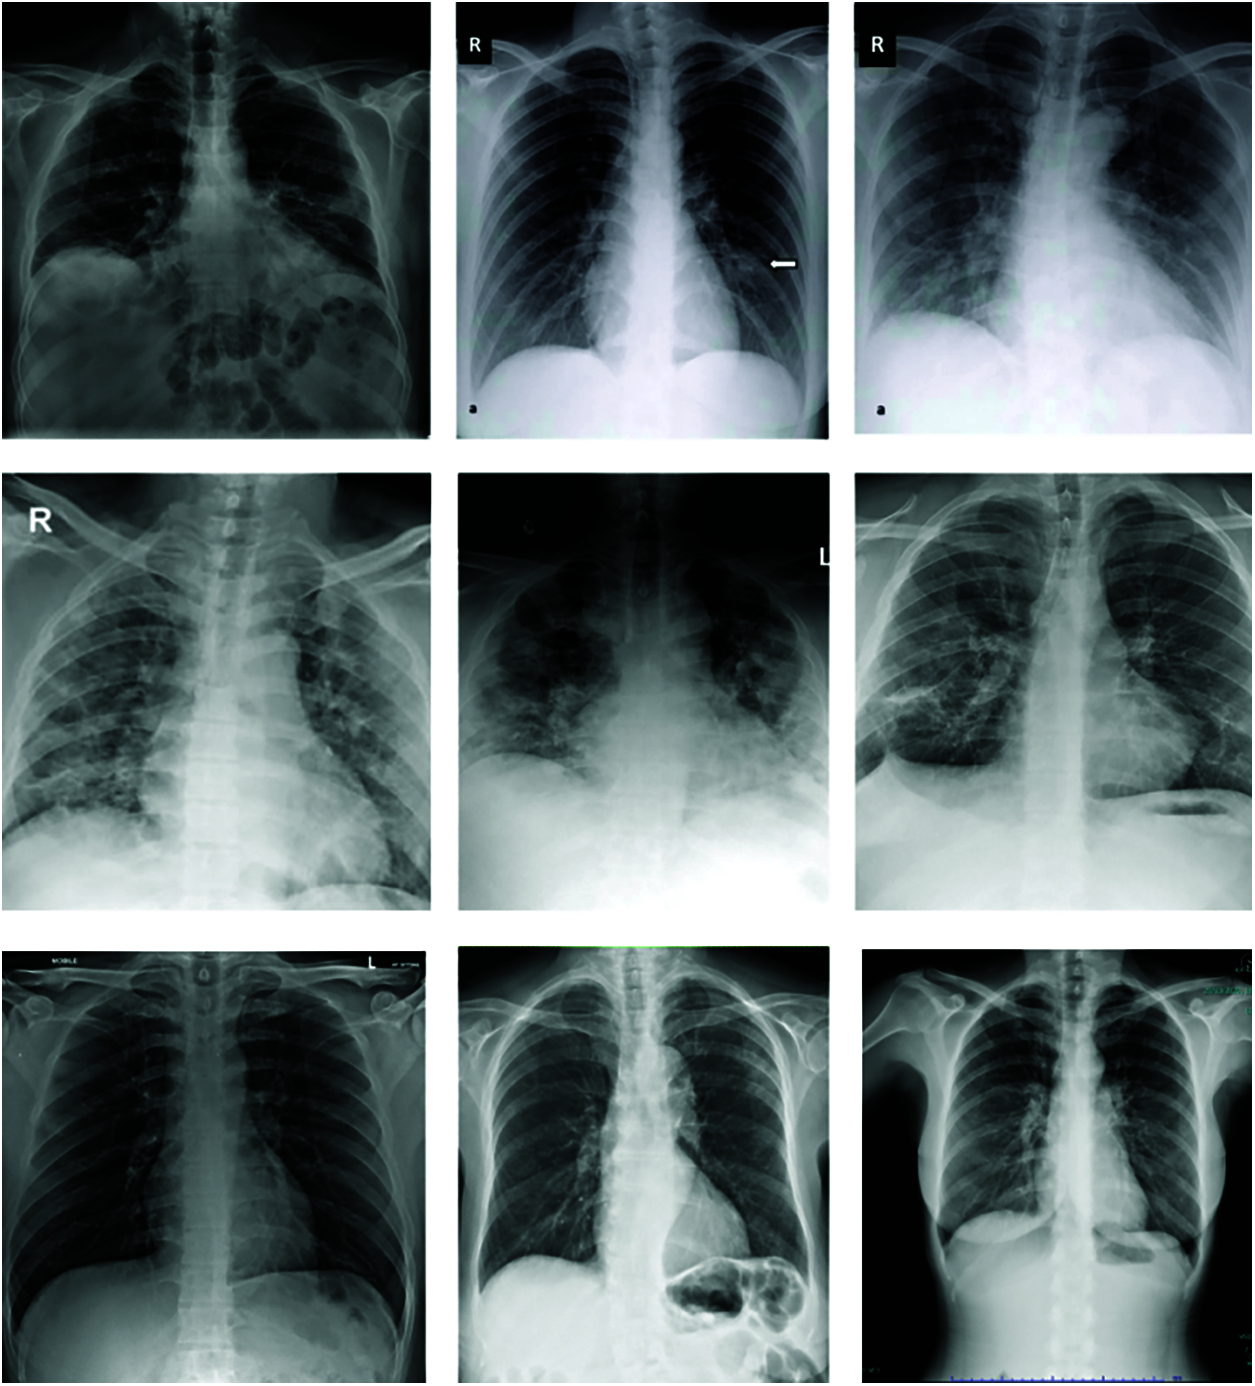

For our experimentation, we mainly used the public dataset obtained from a worldwide collection by Cohen et al. [25]. This dataset consists of chest X-ray and CT images of patients which are positive or suspected of COVID-19 (Figs. 3, 4) or other viral and bacterial pneumonias (MERS, SARS, and ARDS.). Data are collected from public sources as well as through indirect collection from hospitals and physicians [26]. This dataset currently consists of around 504 X-Ray images of COVID-19 positive patients and total 866 images. The GitHub repository associated with the work collects images from websites such as radiopaedia.org, sirm.org, eurorad.org and coronacases.org. It is also open for contributions and all new images are rigorously annotated following Posterior Anterior (PA), Anterior Posterior (AP) and Anterior Posterior Supine (AP Supine) views of the lungs. Additional patient information is also provided such as: patient id, Number of days since the start of symptoms, sex, age, type of pneumonia, RT_PCR_positive, survival, if the patient was intubated , if the patient was in the ICU (intensive care unit) or CCU (critical care unit), if he needed supplemental O2, if the patient was successfully extubated, temperature, pO2 saturation, leukocyte_count, neutrophil_count, lymphocyte_count, modality (CT, X-ray, or something else), Date on which the image was acquired, ‘Hospital name, city, state, country’, the filename, Digital object identifier (DOI) of the research article, URL of the paper or website where the image came from, the license of the image such as CC BY-NC-SA, ‘clinical notes and other notes’). The data in image form that is used to train our model are presented in Tab. 1.

Figure 4: Images X-ray with covid-19